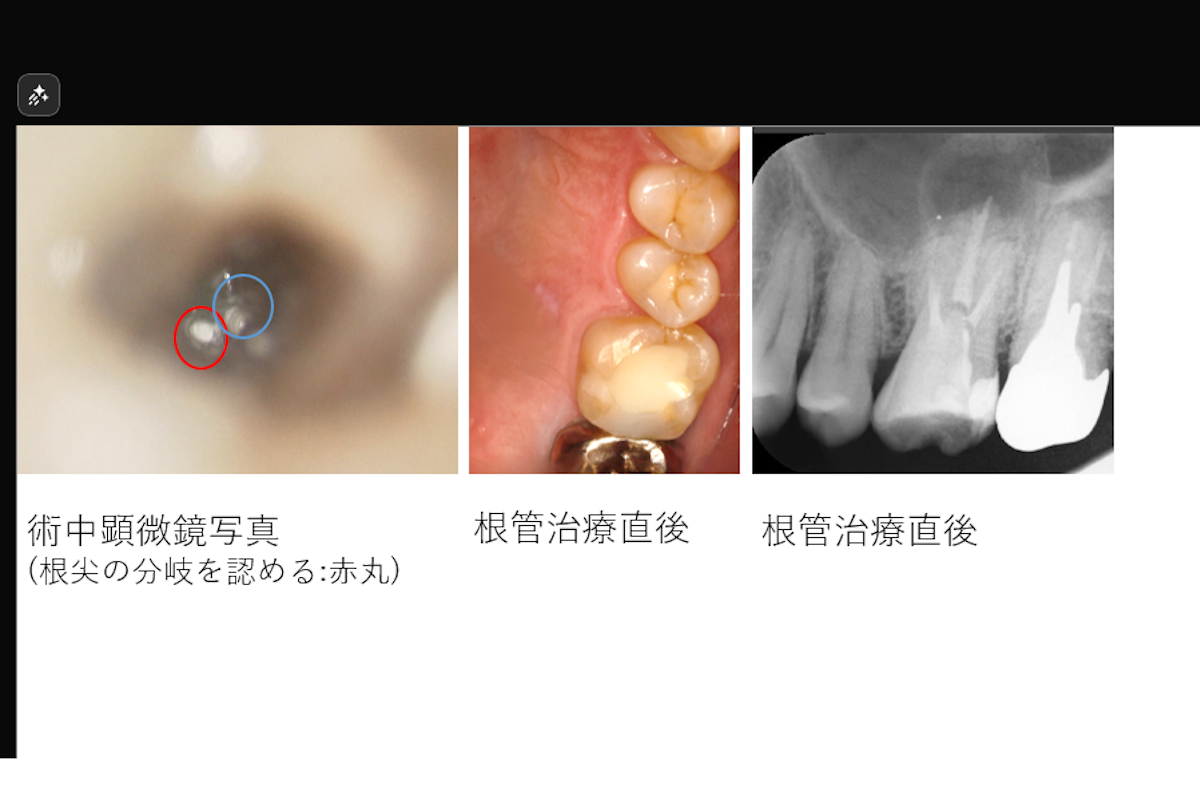

- 治療内容: 上顎右側側切歯 根管治療(MTAを用いた根管充填)